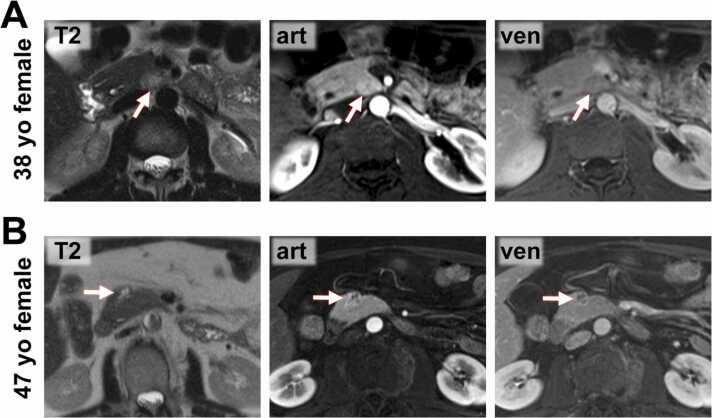

The present study aimed to compare the computed tomography (CT) and magnetic resonance imaging (MRI) features of solid pseudopapillary neoplasms (SPNs) and pancreatic neuroendocrine neoplasms (pNENs).

Lesion imaging features of 39 patients with SPNs and 127 patients with pNENs were retrospectively extracted from 104 CT and 91 MRI scans.

Compared to pNEN patients, SPN patients were significantly younger (mean age 51.8 yrs versus 32.7 yrs) and more often female (female: male ratio, 5.50:1 versus 1.19:1). Most SPNs and pNENs presented as well-defined lesions with an expansive growth pattern. SPNs more often appeared as round or ovoid lesions, compared to pNENs which showed a lobulated or irregular shape in more than half of cases (p<0.01). A surrounding capsule was detected in the majority of SPNs, but only in a minority of pNENs (<0.01). Hemorrhage occurred non-significantly more often in SPNs (p=0.09). Signal inhomogeneity in T1-fat-saturated (p<0.01) and T2-weighted imaging (p=0.046) as well as cystic degeneration (p<0.01) were more often observed in SPNs. Hyperenhancement in the arterial and portal-venous phase was more common in pNENs (p<0.01). Enlargement of locoregional lymph nodes (p<0.01) and liver metastases (p=0.03) were observed in some pNEN patients, but not in SPN patients. Multivariate logistic regression identified the presence of a capsule (p<0.01), absence of arterial hyperenhancement (p<0.01), and low patient age (p<0.01), as independent predictors for SPN.

The present study provides three key features for differentiating SPNs from pNENs extracted from a large patient cohort: presence of a capsule, absence of arterial hyperenhancement, and low patient age.

与pNEN患者相比,SPN患者明显更年轻(平均年龄51.8岁对32.7岁),且女性更为常见(女性与男性比例为5.50:1对1.19:1)。大多数SPN和pNEN表现为边界清晰的病变,呈膨胀性生长模式。与pNEN相比,SPN更常表现为圆形或椭圆形病变,而pNEN在超过一半的病例中呈分叶状或不规则形状(p<0.01)。大多数SPN可检测到周围包膜,但pNEN中只有少数有包膜(p<0.01)。SPN中出血的发生率略高,但无统计学意义(p=0.09)。在SPN中更常观察到T1脂肪饱和成像(p<0.01)和T2加权成像(p=0.046)中的信号不均匀以及囊性变(p<0.01)。pNEN在动脉期和门静脉期的强化更常见(p<0.01)。部分pNEN患者观察到局部区域淋巴结肿大(p<0.01)和肝转移(p=0.03),但SPN患者未出现。多因素逻辑回归分析确定包膜的存在(p<0.01)、无动脉期强化(p<0.01)和患者年龄较小(p<0.01)是SPN的独立预测因素。

本研究从大量患者队列中提取了区分SPN和pNEN的三个关键特征:包膜的存在、无动脉期强化和患者年龄较小。